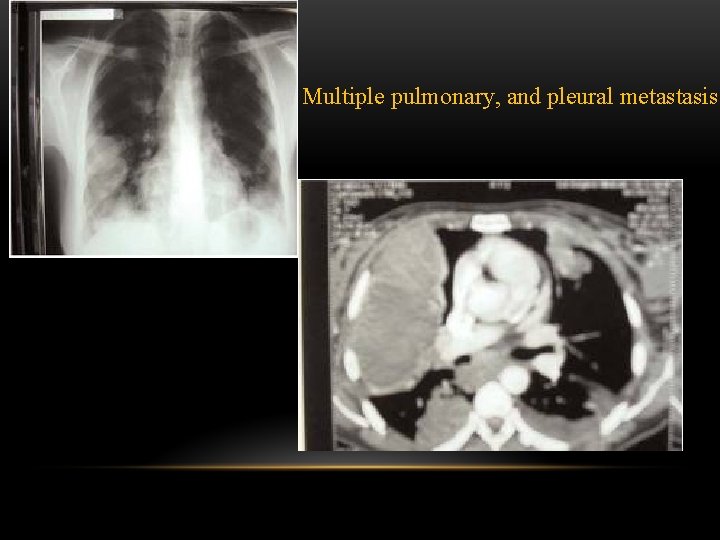

pleural masses Multiple • Pleural metastases. • Asbestos related pleural disease: Look for calcifications. • Malignant mesothelioma. Solitary • Pleural metastases: • Solitary fibrous tumor of the pleura. • Lipoma. • Malignant mesothelioma:

Multiple pulmonary, and pleural metastasis